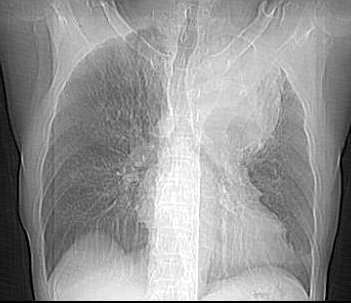

以下是引用乡医在2006-5-15 11:05:00的发言:[br]定位:来自纵隔[br]影象:与纵隔关系密切,类圆形,有膨胀感,有完整的壁及壁结节强化,内部密度均匀。[br]临床:男,60,胸不适半年,近有发热,无咳嗽咳血,平素体健无体检史。[br]影象意见:支气管囊肿合并感染。建议病理确诊。

以下是引用逸风在2006-5-15 17:08:00的发言:[br]ct所见各位老师描述很全面,不再赘述.补充一点,右侧镉肌局限性升高.[br]定位:左后上纵隔.从平片看,肿块外缘肺纹理呈弧形受压改变.横断扫描肿块在肺门周围靠后,肺门及气管位置未见明显移位.外周肺野未见明显阻塞性改变.[br]定性:恶性可能大.肿块边缘不光整,可见强化壁结节,内部有轻度不均匀强化密度,部分层面肿块与主动脉分界不清.右肺中叶小结节影.[br]诊断意见:左侧后上纵隔囊实性占位,考虑来源于神经源性肿瘤,恶性可能大.[br]建议:1.穿刺活检,明确诊断.2.b超右膈下检查,排外膈下病变.